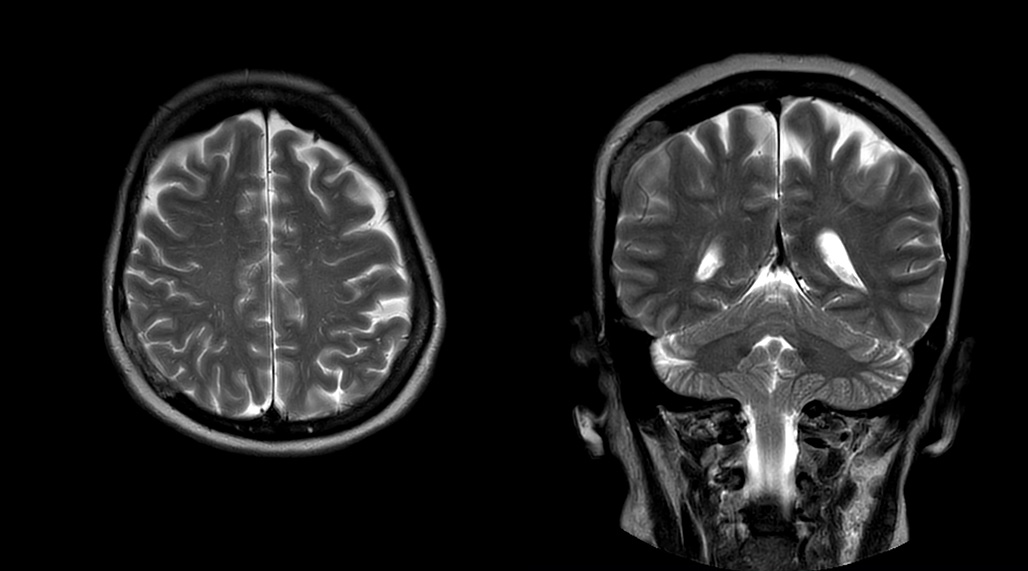

“Without using an endorectal coil we do our prostate MR at 0.5 mm resolution, following the European society of urology protocol [1]. For certain joints we use a virtual arthroscopy protocol with 1 mm pixel size and 2 mm slice thickness. Ingenia really excels in our neurography, brachial plexus and prostate scans. Our neurologists insist on using our 3.0T for those,” Dr. Kaakaji adds.

DMG recognizes MultiVane XD motion compensation is another Philips technique that contributes to image quality and scan efficiency. “We run MultiVane XD for motion-free imaging on almost all our T2-weighted brain scans, just to reduce any repeats we might get. We know our non-contrast brain scans are going to take 20 minutes almost every time,” Mr. Duffy says.

“Using MultiVane XD still allows us to turn on dS SENSE, which significantly cuts scan time compared to what we were doing before,” he adds. “We went from a 2.5 or 3-minute scan to a 1.5-minute scan with no loss in image quality. So, it not only reduces the motion, but also reduces scan time. That gives us a little bit of extra time to speak to our patients and explain the exam a little more.”